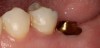

Integrative digital planning can also lead to quicker and more efficient treatment times for dental implant therapy. Another patient presented for a dental implant to replace tooth No. 19 at the end of orthodontic treatment. By leveraging 3D planning (Figure 13) and the printing of a surgical guide, the patient's implant was placed using a flapless approach. At the time of placement, an intraoral scan body was placed on the implant and digital impressions were made for her final restoration (Figure 14). At 10 weeks, the final custom abutment and CAD/CAM crown were delivered, all digitally fabricated without the use of physical models (Figure 15 through Figure 17). For implant placement and restoration, the patient had two visits, with a total chair time of 65 minutes, and no need for anesthetic at the second visit.

Fig 15. Custom titanium abutment No. 19 at delivery.

Figure 15

Fig 16. Final crown No. 19 delivered

Figure 16

Fig 17. Radiograph showing final restoration for implant No. 19.

Figure 17